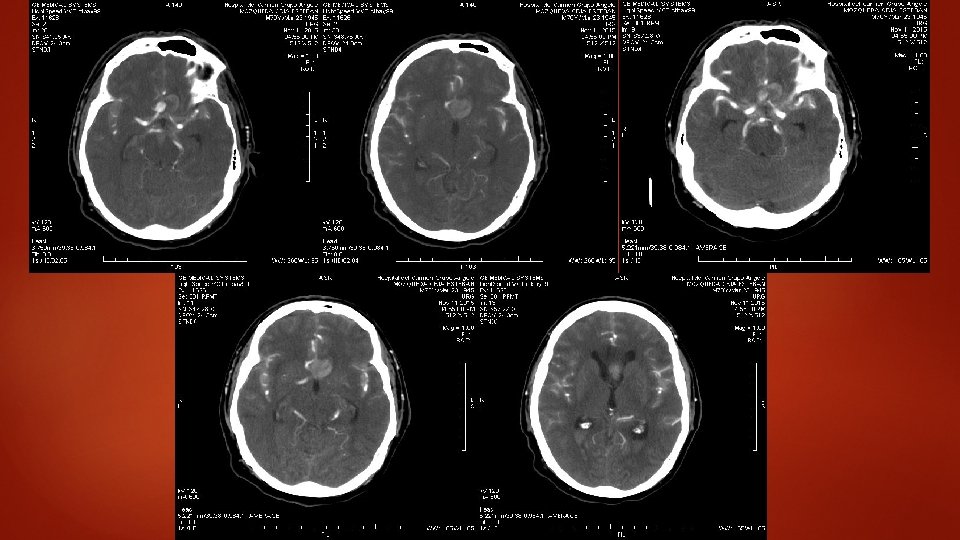

Al llegar al hospital Se decide tomar CT de Cráneo y Angio. CT

Interpretación radiológica BORRAMIENTO DE LOS SURCOS PRESENCIA DE IMÁGENES HIPERDENSAS COMPATIBLES CON HEMORRAGIA SUBARACNOIDEA